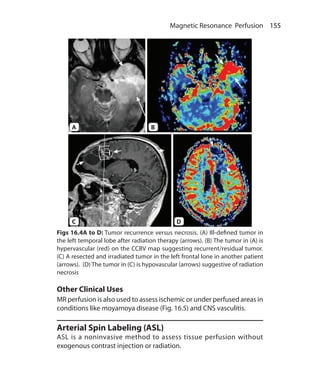

obtained

Fat and white matter are suppressed 3. CSF and water is suppressed

Mainly used in body imaging 4. Used in neuroimaging

Cannot be used in postcontrast

imaging as short T1 tissue are

suppressed and contrast shortens T1